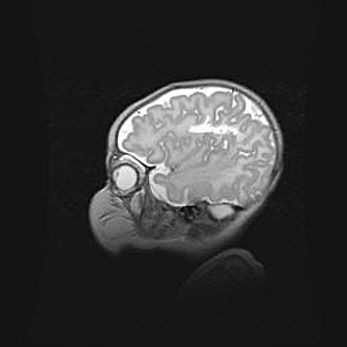

Аномалия Денди-Уокера. Признаки гипоплазии мозолистого тела.

Возраст: 5 месяцев 3 дня

Вес: 5550 г

Пол: мужской

Окружность головы: 39 см

Срок гестации: 40 недель

Аномалия Денди-Уокера – это порок развития головного мозга, для которого характерна триада симптомов: гипотрофия или аплазия червя мозжечка и/или полушарий мозжечка, расширение четвёртого желудочка с формированием ликворной кисты задней черепной ямки, гипертензионная гидроцефалия различной степени.

Гипоплазия мозолистого тела относится к дефектам внутриутробного этапа развития мозговой ткани, возникающим в процессе закладки структур головного мозга, что происходит на начальных этапах развития эмбриона.